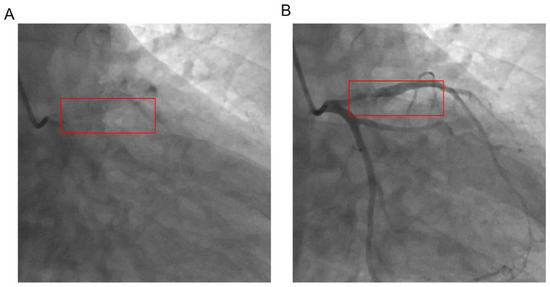

3.6. Comparison of Coronary Angiography Results between the Two Groups (Figure 1 and Table 5)

The two groups showed statistically significant differences in the SYNTAX II score and Mehran in-stent restenosis classification (p < 0.05). The Mehran classification was predominantly type I and II for the L-NLR group and type I and II for the H-NLR group. No significant differences were observed in the number of branches with previous lesions, type of stent drug coating, pre-procedural Gensini score, SYNTAX score before the first PCI, number of branches with the current lesion, number of stents, stent diameter, stent length, and interval duration.

Figure 1. Coronary angiography stent and stenosis location. (A) Stent position, (B) in-stent restenosis position.